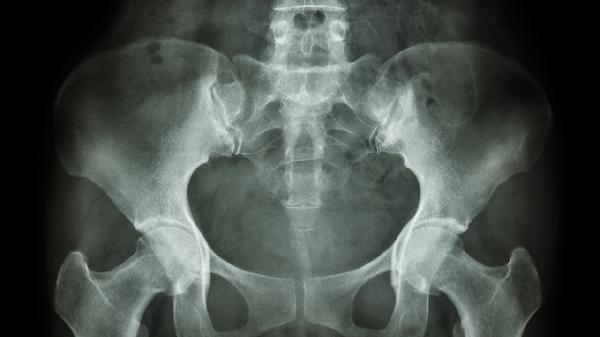

骨科骨盆和髋部特殊检查方法主要有托马斯试验、4字试验、髋关节撞击试验、骨盆挤压分离试验、髋关节弹响试验等。这些检查方法有助于评估髋关节活动度、稳定性及是否存在病变。

骨盆挤压分离试验可判断骨盆环稳定性。患者侧卧,检查者双手置于髂嵴处施加垂直压力,若诱发疼痛提示骨盆骨折或骶髂关节损伤。阳性者可能伴有下肢不等长、负重困难等症状。急性外伤患者实施时需谨慎,避免二次损伤。